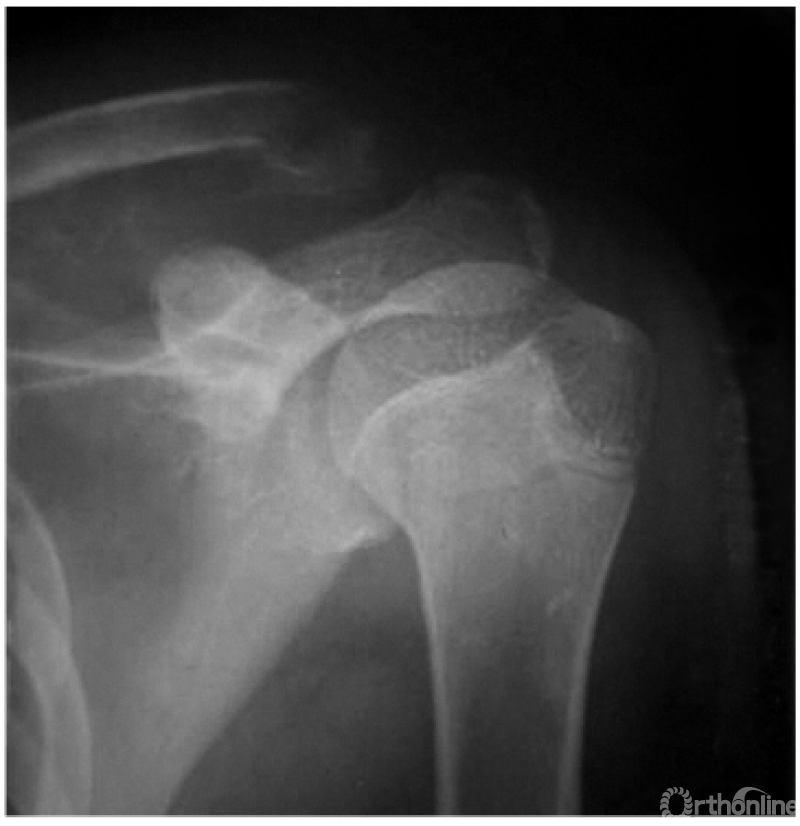

2. 锁骨外段骨折

本例虽系外段骨折,但由于喙锁韧带断裂亦可引起锁骨近折端向后上翘起(图2)。